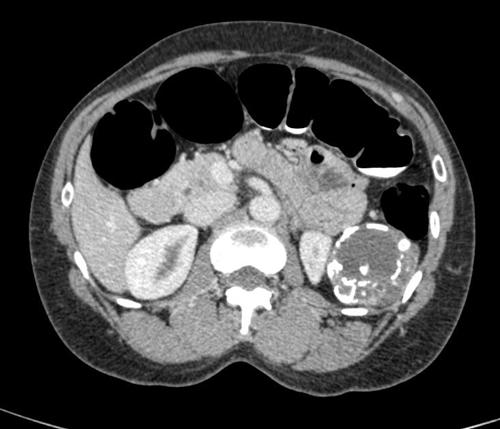

相关图片